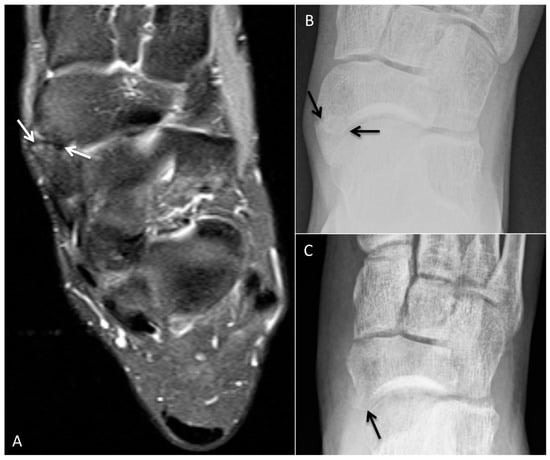

4.1. Accessory Navicular Resection